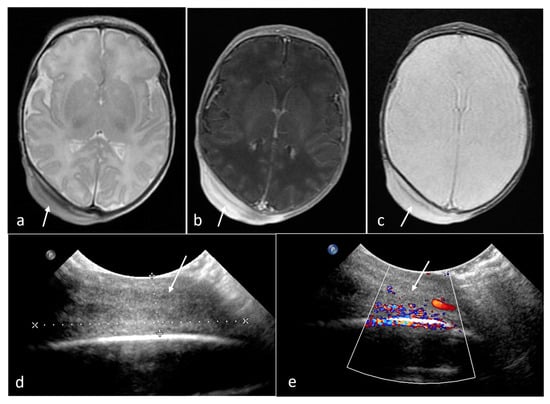

| Rhabdomyoma | heart | 22 | 5.08 [0.1–22] | no | Solid | No | N/A |

| Subependymal giant cell astrocytoma | foramen of Monro | 6 | 0.74 [0.59–0.89] | no | Solid | yes (2/2) | N/A |